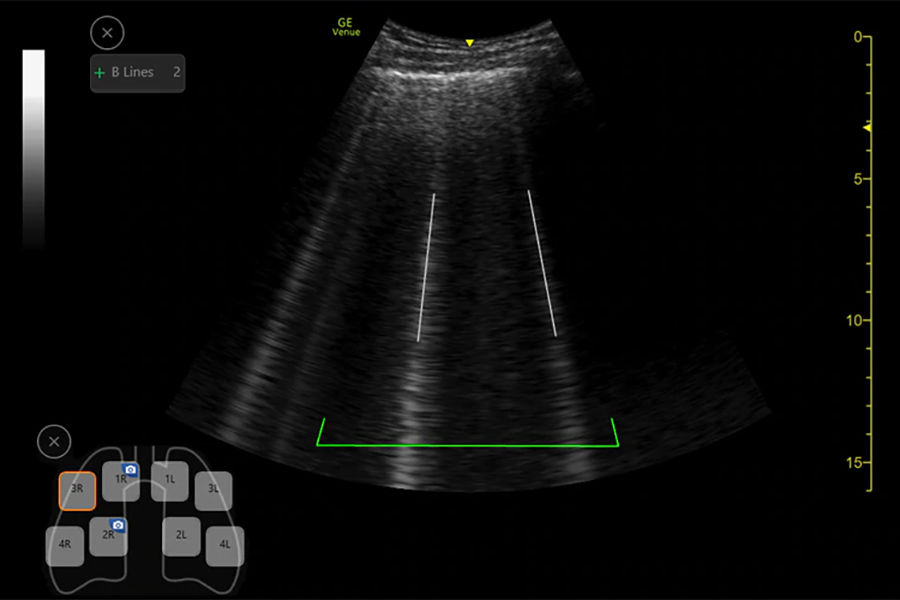

PHYSIOLOGISCHE BILDGEBUNG

Das Ultraschallgerät Auto-B Line bietet diagnostische Unterstützung bei Atelektase, Lungenergüssen, Lungenödem und/oder Lungenentzündung und liefert den gesamten Lungenwert in einem einzigen Schritt.14